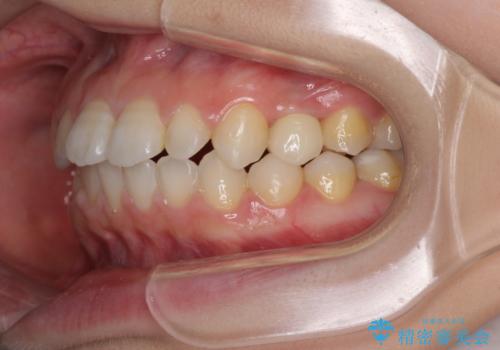

- 歯の欠損による隙間だらけの歯並びを気にして来院された患者様です。

上顎左右1本ずつ欠損していたため、歯列矯正により欠損部位にスペースを集め、その後欠損部位をインプラントにて補綴することとしました。

インビザラインによる矯正治療も提案しましたが、長時間の装着や自己管理が難しいとお考えで、ワイヤーによる矯正治療を行いました。

歯並びは比較的早めに整いましたが、インプラントを埋入するにあたって前後の歯根位置を改善する必要があり、矯正治療に期間を要することとなりました。